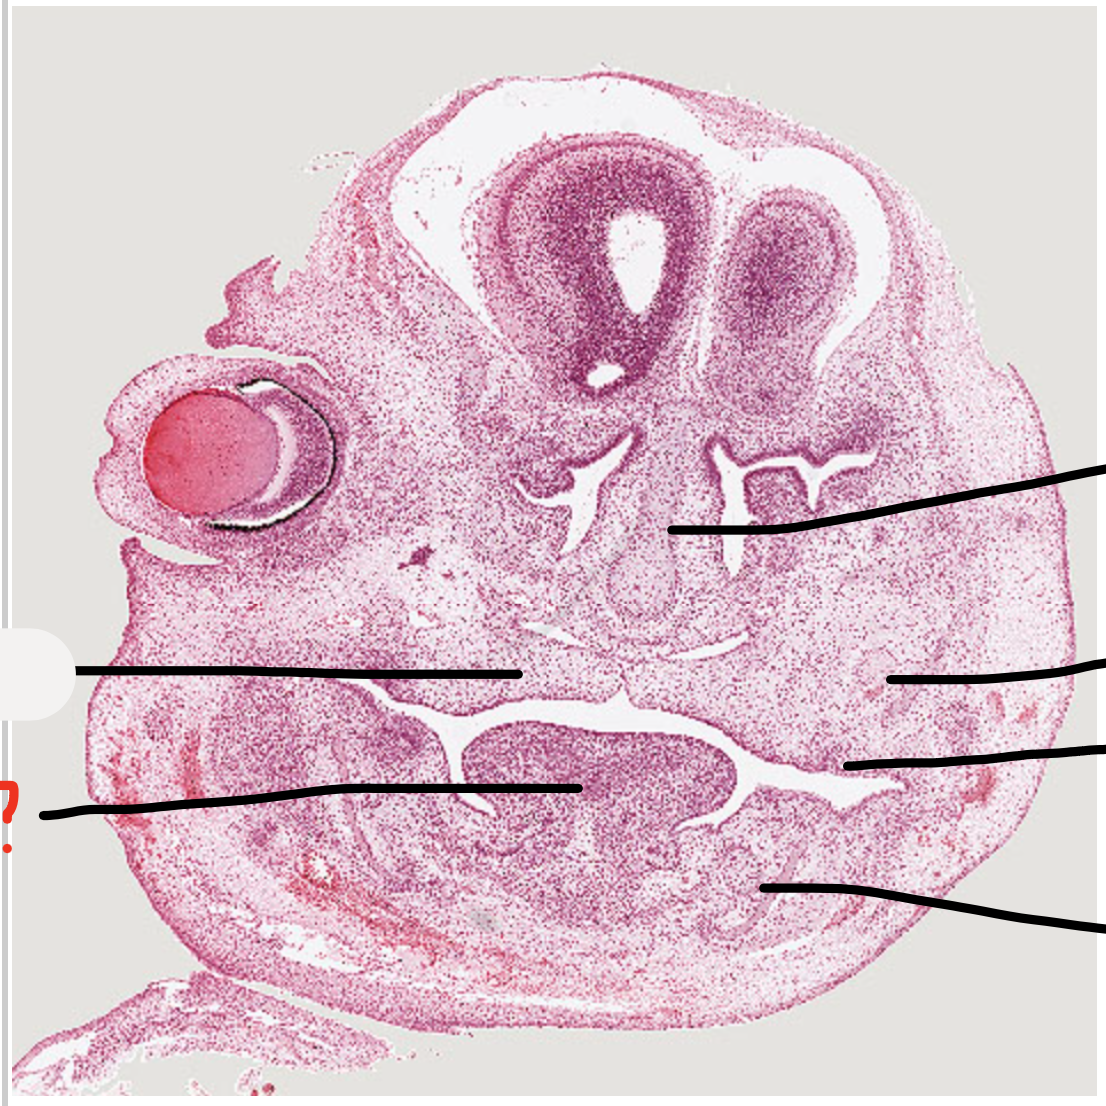

3

Q

A

developing tooth -> dental lamina and tooth germ

4

meckel’s cartilage

5

tongue

6

palatal shelves

7

maxillary nerve trunk